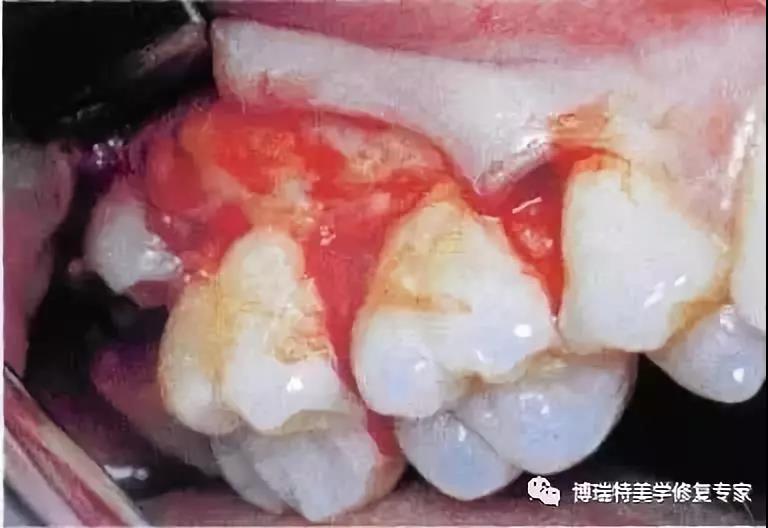

2、翻瓣后,阻生牙的(牙合)面位于第二磨牙颈部及其牙槽嵴顶均清晰可见。切割牙体前先去除舌侧骨板以保护软组织。

3、使用纺锤形的车针,显露其最大周径至釉牙骨质界。车针末端应进入牙槽窝内壁。

4、分牙前应认真确定分牙沟的位置:沿牙体长轴垂直(牙合)面至根分叉。用上述的车针分牙。切割至牙冠舌侧时应格外小心。

5、分牙已基本完成,远中牙片挺松后即可顺利取出。

6、远中牙片取出后即可拔除近中部分。术后应注意牙槽嵴顶的高度,保留颊侧骨板很重要,有利于牙槽窝和第二磨牙牙槽骨的完全重建。